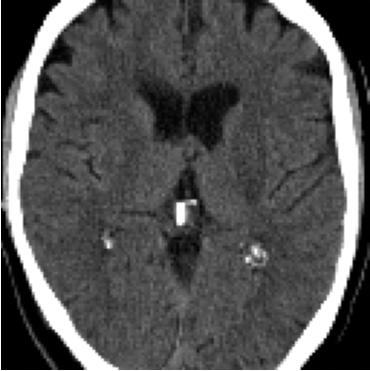

The former is a randomised-controlled trial that collected brain imaging data, primarily CT scans, from 3035 patients exhibiting stroke symptoms. The scans were conducted at two time points: immediately after the patients’ hospital admission and again between 24-48 hours later. Radiologists involved in the trial assessed the presence or absence of early ischemic signs and recorded the location of any identified lesions for positive scans. In our analysis, we considered a total of 5681 scans, of which were classified as negative (no lesion), while the remaining scans were positive. In particular, We considered 11 slices for each scan and resized each slice to . For more detailed information about the trial protocol, data collection, and the data use agreement, please refer to the following URL: IST-3 information.

As annotations of lesions are not available in IST-3, we utilise this dataset primarily for qualitative evaluations. On the other hand, for the BraTS2021 dataset, we have access to lesion annotations, enabling us to conduct quantitative analysis of the anomaly maps that we create. Both datasets were divided into training, validation and test sets with a 70-15-15 split.

4.3 Counterfactual Examples

In Figures 2 and 4 we display examples of healthy images and anomaly maps obtained with the different approaches. We can observe that f-Ano GAN is not able to generate credible counterfactuals and generally produces images of poor quality and unrealistic appearance. On the other hand, the approaches based on diffusion models are able to create more high-quality results. However, the ones obtained with CG and CFG seem to present some artifacts, which may not only impact the realism of the counterfactual examples but also the precision of the anomaly maps obtained from them. In order to better quantify the capability of these methods to accurately segment pathological areas, we compute the Dice scores of the anomaly maps they generate.